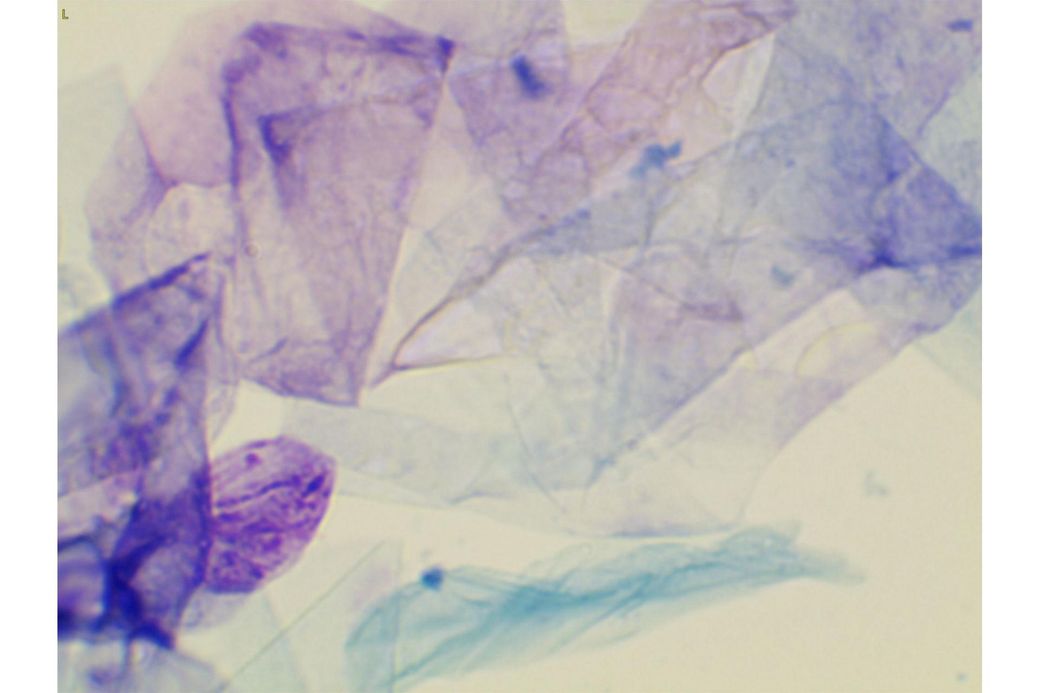

오늘 낮과 방금 5분전에 일어난 일인데요.. 강아지 귀질환 중에.. 옷입히고나서 귀를 바닥에 대고 비비거나, 귀에 통증을 호소하면서 잠깐 비틀비틀 걷는 경우 이런 경우 대체 뭘까요? 외이염일때도 이럴수도 있을까요? 아니면 중이염 내이염일지.. 한 2~3분정도 통증을 호소하다 지금은 또 정상이 됬는데 옷입을때만 옷의 목카라 부분이 귀에 닿을때 문제가 되는 느낌입니다. 평상시엔 가끔 양쪽 귀를 긁거나 귀를 자주 터는 정도입니다. 특이사항은 오른쪽귀 솜 돌돌 말아 귀안에 넣어줘도 비명을 지르며 엄청 아파하는데(작년11월경) 왼쪽은 안아파합니다)

mri ct 말고는 죽어도 중이염 내이염 또는 고막 확인이 불가능한가요?

제가 가장 알고싶은점은. 저렇게 옷깃에 귀가 시쳐도 아파할정도면 이게 외이염일까요 중이염일까요 내이염일까요? 얼마나 아픈지 옷한번 얇은 내복 평상시 입던거 입히면 입히고 나서 바로 온집을 돌아다니면서 바닥에 귀를 대고 정신나간애처럼 비비고 비틀비틀 걷습니다 그러다가 2~3분후 다시 정상으로 돌아옵니다